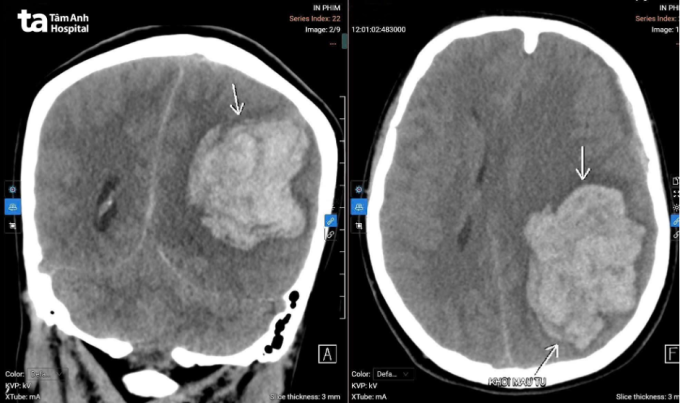

Loan cấp cứu tại Bệnh viện Đa khoa Tâm Anh Hà Nội trong tình trạng hôn mê sâu, mất phản xạ, chỉ số tri giác 6 điểm (người bình thường 15 điểm). Đồng tử trái giãn 4 mm mất phản xạ ánh sáng, đồng tử phải 3 mm đáp ứng yếu, liệt hai bên cơ thể. Kết quả chụp CT có khối máu tụ trong não cấp tính kích thước lớn tại bán cầu trái (khoảng 78×59×57 mm). Tình trạng phù não lan rộng, chèn ép lều tiểu não trái, thoát vị thái dương trong gây đè ép thân não. Lớp máu dưới màng cứng bán cầu trái dày khoảng 7,5 mm. Nguyên nhân chảy máu từ khối dị dạng mạch não.

Ảnh chụp CT sọ não cho thấy xuất huyết ở nhu mô não bên trái. Ảnh: Bệnh viện Đa khoa Tâm Anh